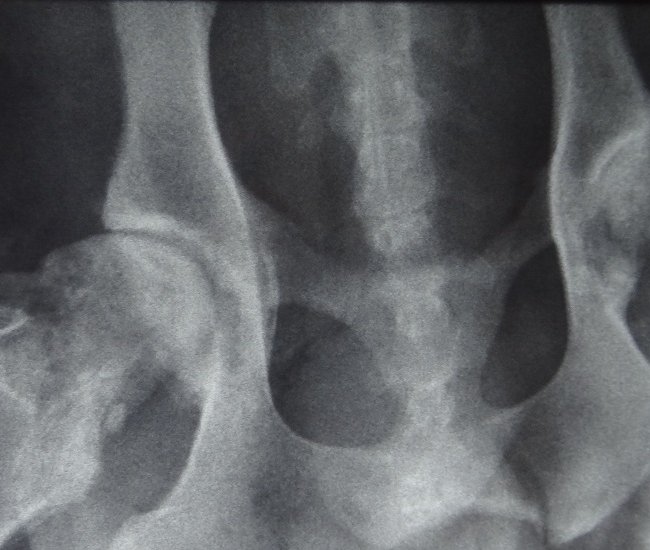

- Diferentemente do raio-x analógico, este raio-x oferece altíssima definição e todas as vantagens da tecnologia digital. É possível aproximar a imagem, trabalhar o contraste, exposição.O software permite ainda avaliações da medida cardíaca do animal e graus de displasia coxofemoral, por exemplo – explica o Dr. Nardeli Lucena.

- sofware com medidas para avaliações do tamanho cardíaco e medições dos ângulos de Norberg para diagnóstico e classificação de displasias coxofemorais;